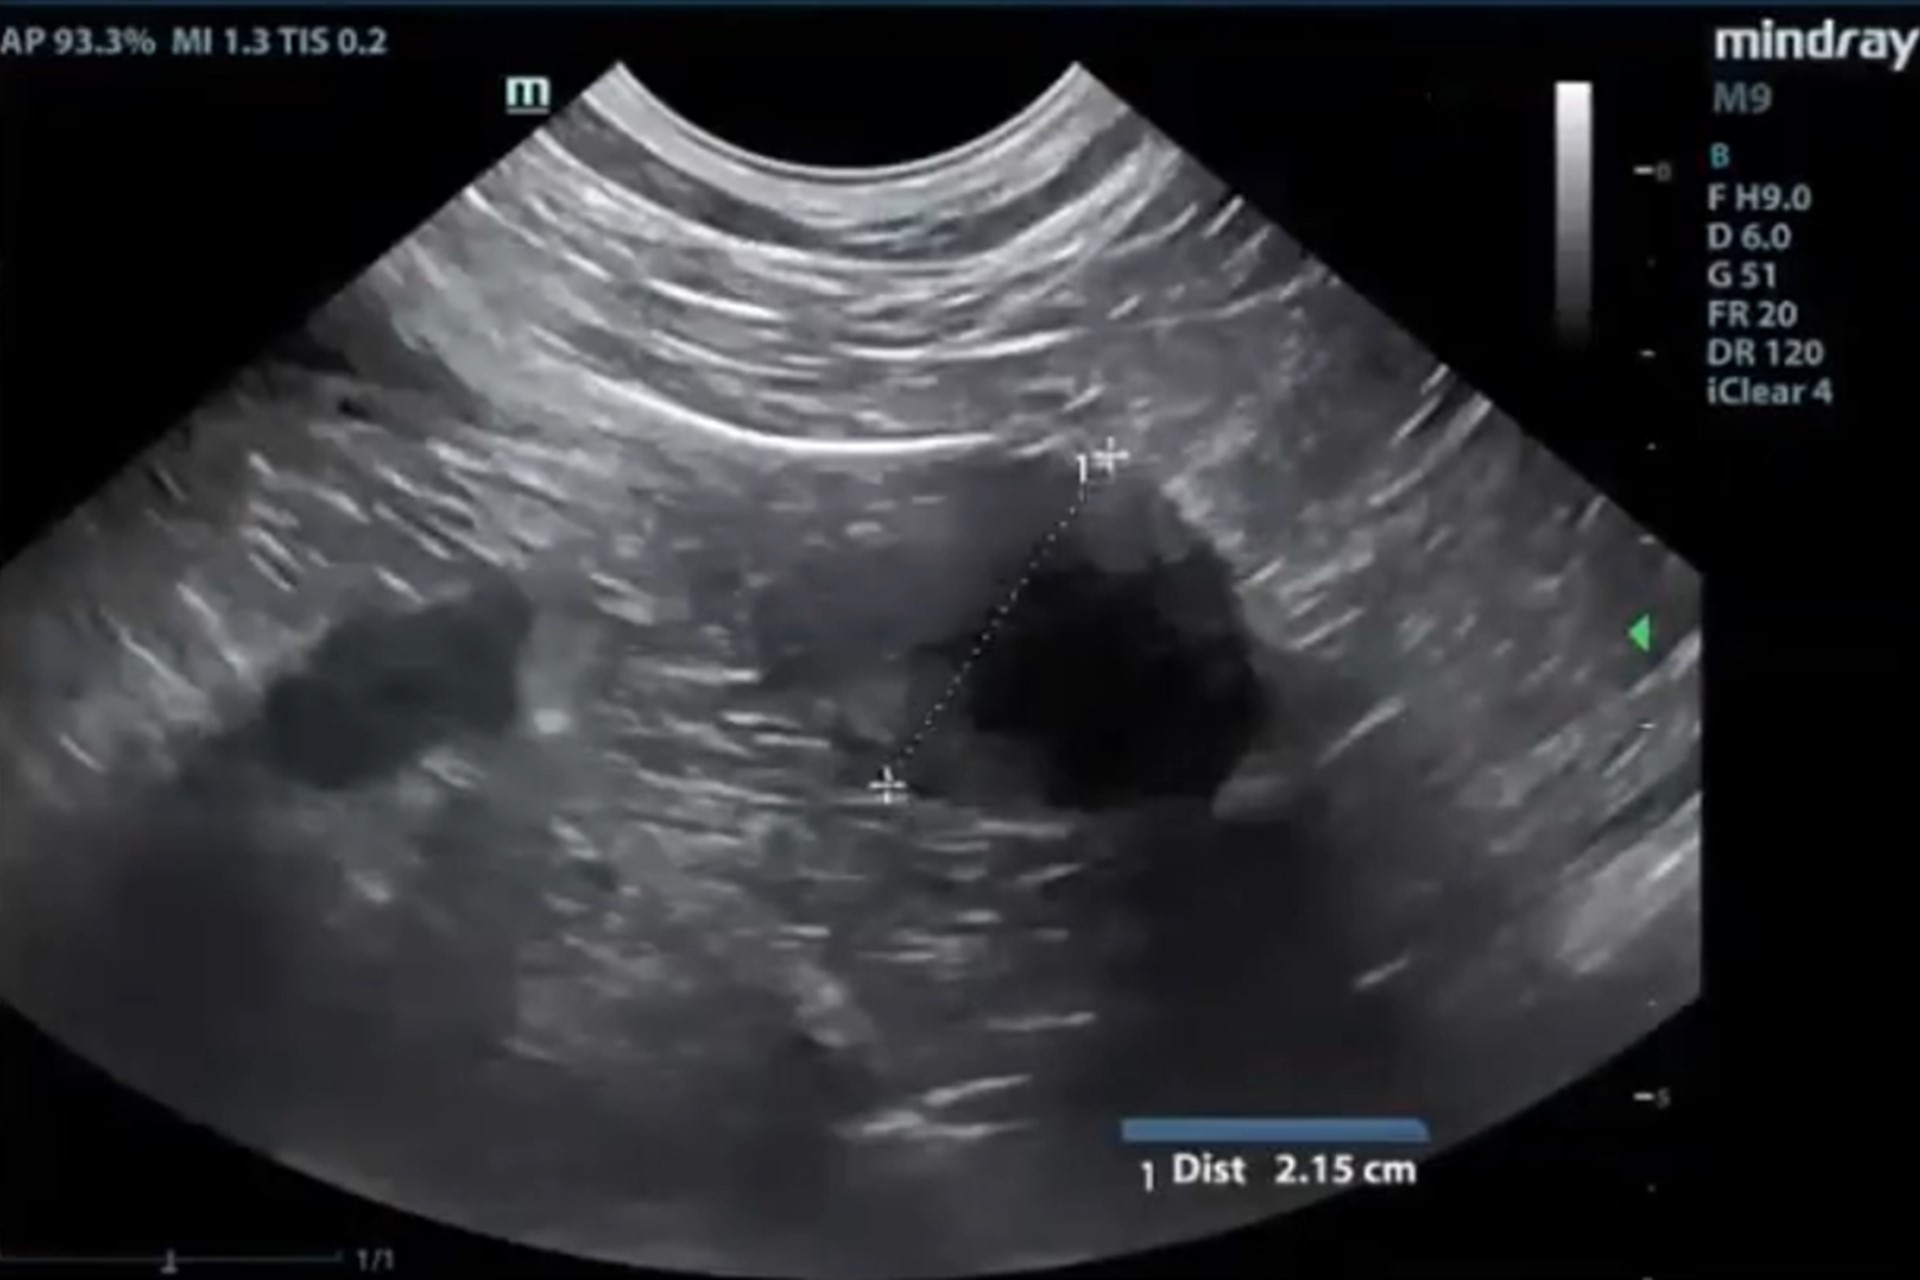

Ecografía abdominal

Evaluación detallada de todos los órganos abdominales. Permite detectar masas, cuerpos extraños, procesos inflamatorios, alteraciones urinarias o reproductivas, así como enfermedades hepatobiliares o gastrointestinales.